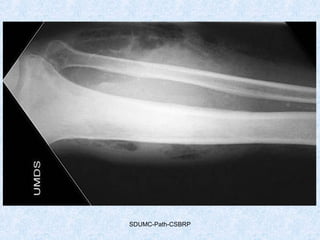

• #66 Gas gangrene Findings There is extensive gas in the soft tissues of the lower leg. There is arterial calcification visible, consistent with the known diabetes. The appearance are those of gas gangrene, which is more common in diabetics. Treatment includes antibiotics (penicillin) and prompt amputation.